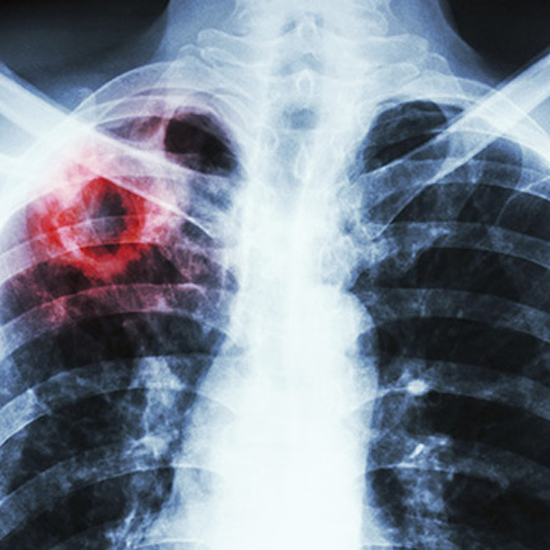

Україна має один із найвищих рівнів захворюваності на хіміорезистентний туберкульоз у світі та посідає третє місце за абсолютною кількістю зареєстрованих випадків туберкульозу із розширеною резистентністю.